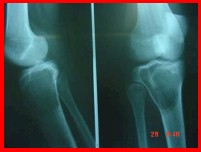

Tumor de Células Gigantes:

Epifisario. Excéntrico. Esclerosis marginal. Agresivos. Las lesiones se consideran entre benignas y malignas. Adolescentes Se hace curetaje y fenolizaciones.

Figura 16: tumor de células gigantes